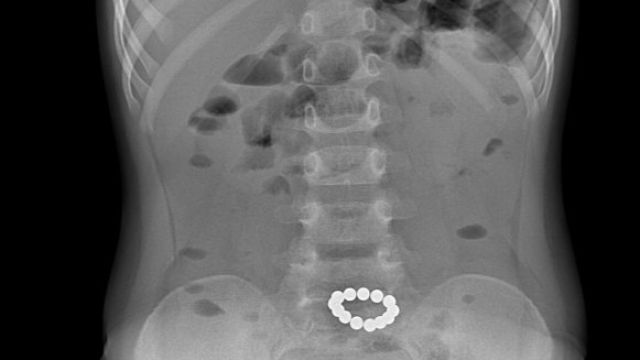

Фото: Минздрав РК | Telegram

Эти игрушки, состоящие из мелких магнитных шариков, могут представлять серьёзную угрозу для здоровья и жизни ребенка, сообщили в крымском Минздраве.

Нередко дети проглатывают эти шарики, и они склеиваются между собой, вовлекая в этот процесс стенки кишечника. Это требует немедленного оперативного вмешательства, после которого дети находятся на длительном лечении в отделении реанимации.

В худшем случае, это может привести к образованию свищей, через которые содержимое кишечника может выходить в брюшную полость, а также к развитию непроходимости кишечника.